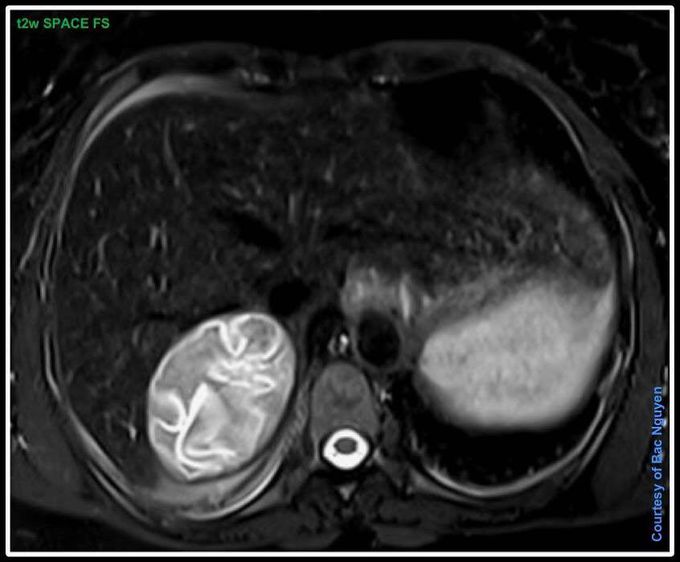

Tapeworm (Echinococcosis Hydatid Cyst) @ Siemens 1.5T Aera I wonder how this would have look like with a dynamic truefisp……..#Siemens_MRI#siemens #mri #tapeworm